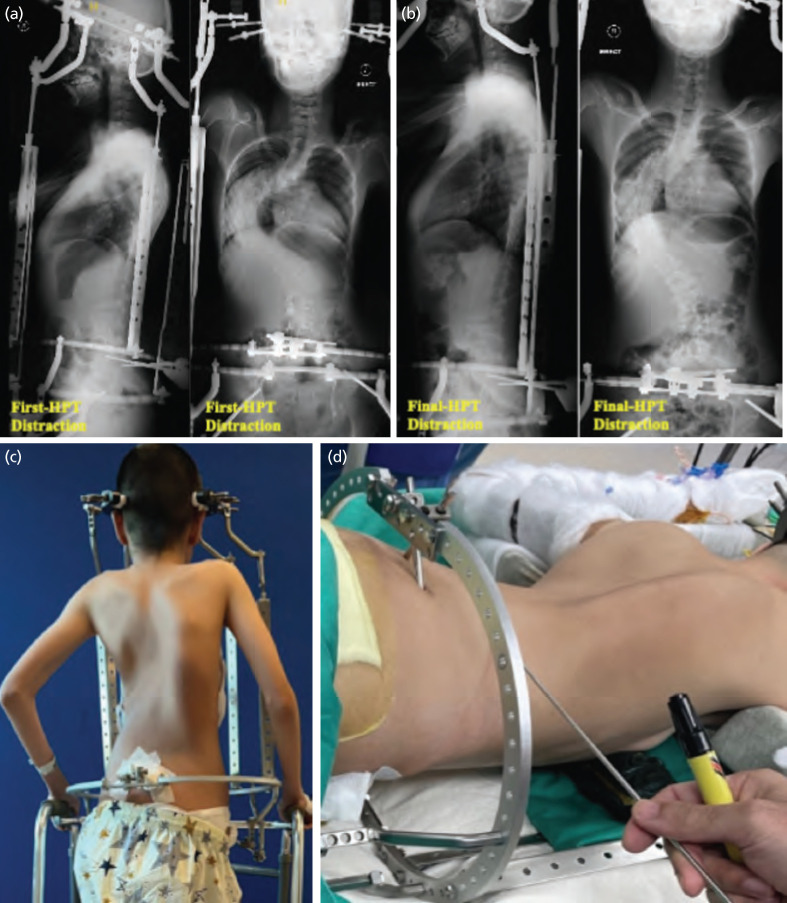

Neglected severe rigid kyphoscoliosis can lead to rapid curve progression, presenting a challenge for surgical correction and carrying higher risks of mortality, morbidity, and neurological injury, potentially resulting in permanent paralysis. Halo-pelvic traction (HPT) has been reported to be effective in improving curve flexibility, assisting the surgical correction process, and reducing the likelihood of neurological complications. We report the case of a 15-year-old girl with mosaic Turner syndrome and severe kyphoscoliosis, who experienced progressive curve progression (from 41° to 158°) over a span of 6 years. Preoperative halo gravity traction (HGT) was unsuccessful. To address this deformity, HPT was performed with CT-based navigation for pelvic pin insertion, considering her relatively small pelvis and pelvic obliquity. This technique allowed for precise pin placement, reducing the risk of injury to major arteries, nerves, and abdominal/pelvic organs, while enabling the creation of a more versatile halo-pelvic frame designed to enhance patient comfort and mobility. The patient underwent weekly distraction using HPT for 4 weeks, during which her coronal Cobb angle reduced from 158° to 103° and her kyphotic angle decreased from 90° to 64°. With this notable improvement in the primary spinal curvature, we proceeded with posterior spinal fusion. Notably, this approach obviated the need for vertebral column resection. As a result, we achieved a correction rate of 53.8% in the coronal Cobb angle and 55.6% in the kyphotic angle without neurological injury.